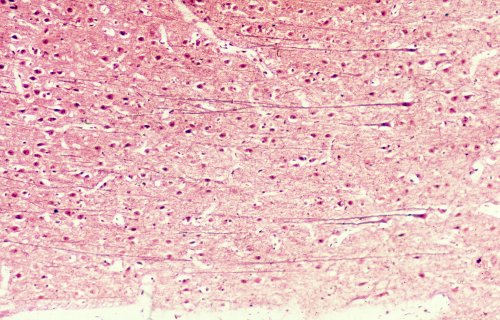

A high magnification of the cortex showing the cells of Retz (large pyramidal cells).